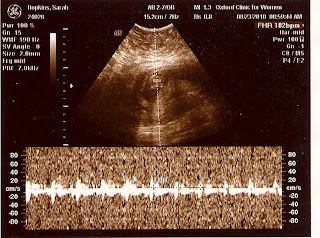

As to the purpose of the visit: her heart looks great.  They spend a great deal of time on this.  There are a number of techniques involved.  A simple ultrasound can show the heart moving as it beats, and the valves opening and closing.  The machine can also detect the movement of blood through the major blood vessels as well as between the chambers of the hearts.  Finally, they can zero in on and listen to the various components of the heartbeat: this or that valve opening and closing in rhythm.  The amount of detail that can be gleaned is really impressive, given baby's heart is about the size of a quarter.

Put all these approaches together and you get the result you want: baby is healthy, and her heart is in perfect working order.